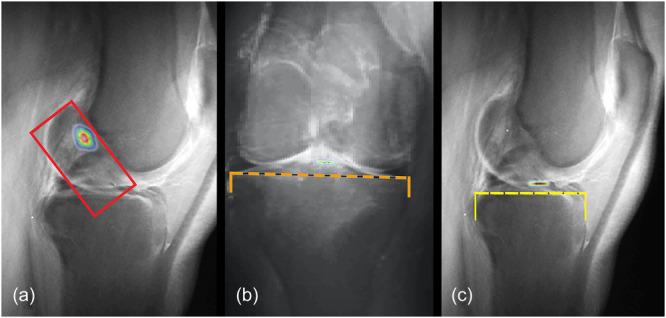

用于个性化前交叉韧带足迹识别的CLASS磁共振成像验证

Validation of CLASS MRI for personalized ACL footprints identification.

In modern anterior cruciate ligament (ACL) surgery, the focus is usually on anatomical reconstruction to restore the natural kinematics of the knee. The individual optimal positioning of the ACL footprints (FPs) in primary surgery is still controversial and, especially in revision surgery, difficult to realize surgically. In this regard, a new MRI-based sequence, the Compressed Lateral and anteroposterior Anatomic Systematic Sequence (CLASS) with marked femoral and tibial FPs as a template, could help. The purpose of this study was to (1) validate the reliability and reproducibility of the localization of femoral and tibial FPs of ACL in the generation of CLASS and (2) compare the identification of ACL FPs by CLASS with previously described methods.

在现代前交叉韧带(ACL)手术中,重点通常是进行解剖重建以恢复膝关节的自然运动学。初次手术中ACL足迹(FP)的个体最佳定位仍存在争议,尤其是在翻修手术中,手术上难以实现。在这方面,一种基于MRI的新序列,即带有标记的股骨和胫骨FP作为模板的压缩外侧和前后解剖系统序列(CLASS)可能会有所帮助。本研究的目的是:(1)验证在生成CLASS时ACL股骨和胫骨FP定位的可靠性和可重复性;(2)将CLASS对ACL FP的识别与先前描述的方法进行比较。

Compressed Lateral and anteroposterior Anatomical Systematic Sequences «CLASS»: compressed MRI sequences with assessed anatomical femoral and tibial ACL's footprints, a feasibility study.

压缩的外侧和前后位解剖学系统序列《CLASS》:评估股骨和胫骨前交叉韧带足迹的压缩磁共振成像序列,一项可行性研究